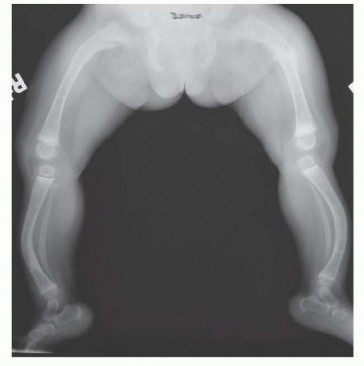

## Full-length radiographs of both legs on the same cassette from the hips to the ankles are ideal to assess areas of fractures and degree of deformity.

## Radiographs of the lower extremity should be performed with the patellas directly anterior and also with the legs maximally externally rotated. This helps assess the severity of the disease, can help predict risk of fracture, and is useful in preoperative planning for osteotomies and instrumentation (FIG 2).

FIG 2 • Typical bowing deformity of the femurs and tibias caused by preexisting deformity and recurrent fractures is accentuated by the pull of the flexors, including the hamstrings and gastrocnemius-soleus complex. Note sclerosis in the medullary canal of the right tibia.